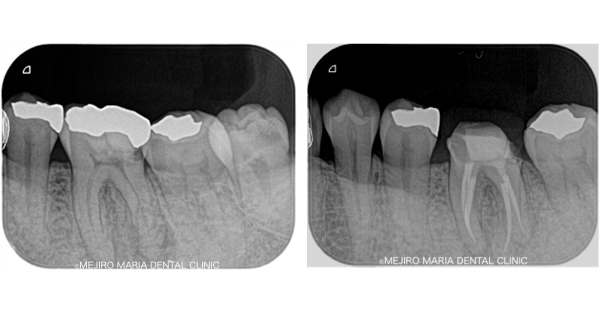

【初回根管治療(抜髄)神経をとる

治療】

初めて歯の神経(歯髄)を取り除く処置です。歯髄炎の症状は抜髄処置を施すことで改善されます。また、根管内の細菌感染が再根管治療よりはまだ少ないので、治療の成功率が高い時期でもあります。根尖性歯周炎の罹患を最小限にすると同時に再根管治療を不要にすることで将来的に歯を最大限保存することにつながるため、再根管治療に比べると精密根管治療の費用対効果が高くなります。

副作用・リスク

• 治療後歯髄炎が進行し痛みを伴う場合根管治療が必要になる可能性があります

• 将来的に再度歯髄炎に罹患した場合、根管治療が難しくなる場合があります

• 術後の経過観察で歯髄に生活反応が見られない場合は根管治療を行う必要があります